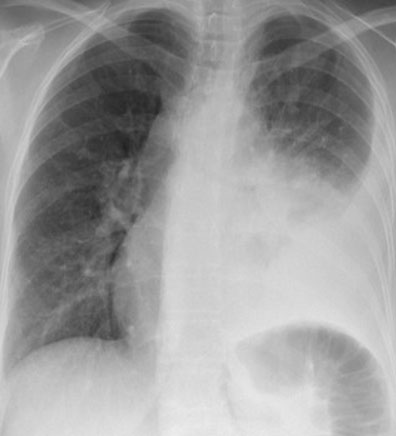

A 37-year-old Caucasian, non-English speaker, presented to her local emergency department twice in 2022 with chest pain and hemoptysis. She underwent investigations including an electrocardiogram (ECG), chest X-ray (CXR), and blood tests all of which were normal. A working diagnosis of musculoskeletal chest pain was made. She had no significant past medical history. She was a heavy smoker (25 pack year history). At the start of February 2023, when she was 26 weeks’ gestation in an unbooked pregnancy, she presented to her local hospital after developing a cough. She received antibiotics for a presumed chest infection. She did not notice any improvement in her symptoms, developed pleuritic left-sided chest pain, reported hemoptysis and presented to the maternity unit at a tertiary center two weeks later. She was noted to have a sinus tachycardia on admission (heart rate 117 bpm), her other observations were within normal limits. Routine blood tests revealed a white cell count (WCC) of 11.6 × 109/L, neutrophil count 8.9 × 109/L, C-reactive protein (CRP) 119 mg/L, urinary legionella and pneumococcal antigens were negative, sputum grew commensals only. Chest X-ray on admission showed a left-sided pleural effusion with consolidation (Figure 1). A temporary chest drain drained 1 L of fluid. She was treated for a chest infection with intravenous co-amoxiclav.

Figure 1: CXR on admission revealing left-sided pleural effusion.